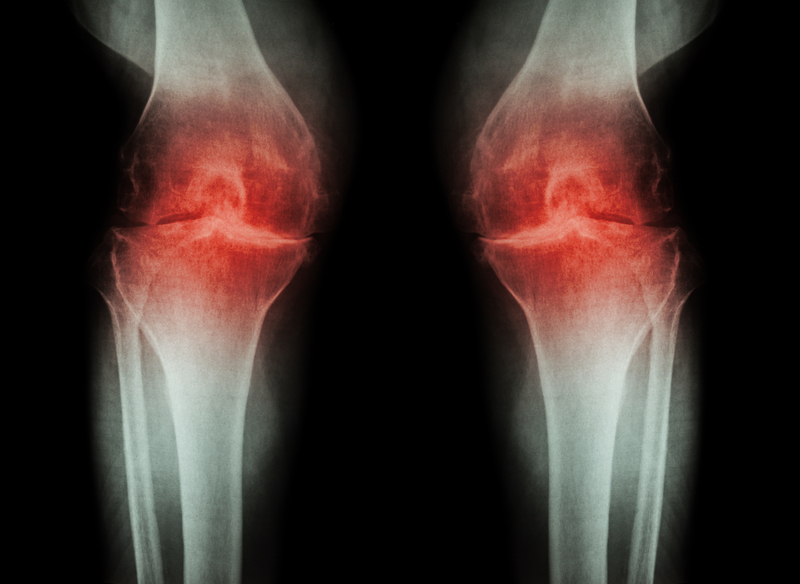

1. Bone Spurs

Osteophytesor bone spurs are small and appear as bumps which protrude from joints affected by osteoarthritis. They are caused when the body tries to mend the breakdown of cartilage. The impact on nearby nerves can create additional problems, including numbness, tingling, and additional pain. This can occur in the spine and lead to difficulty standing and walking, but some people are not even aware of them until they show up on an X-ray.